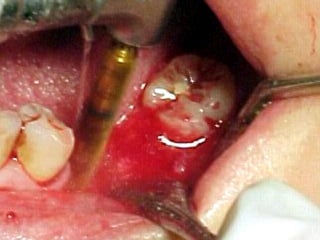

Primer tiempo quirúrgico; Exposición del maxilar para tomar una impresión del

hueso y poder elaborar la estructura implantaria.